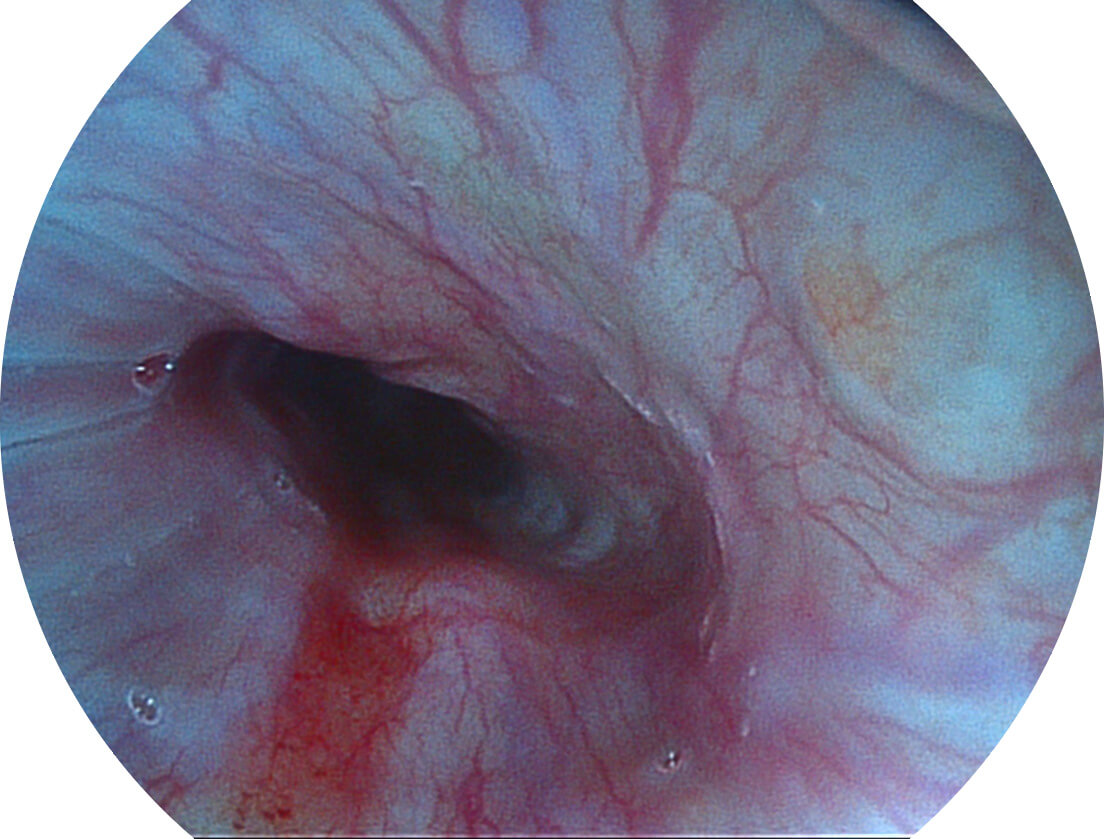

Spectral Focused lmaging, SFI

图像具有高亮度、高黏膜血管颜色对比度的特点,且不改变粘液、食物残渣、粪便的基本颜色,可在中远景下进行观察,助力消化道早期疾病的诊断。

SFI图像

采用光路合束技术,光谱自由度高,实现了更丰富的照明模式,染色模式SFI及VIST,从远景到近景,助力消化道早期疾病诊断。